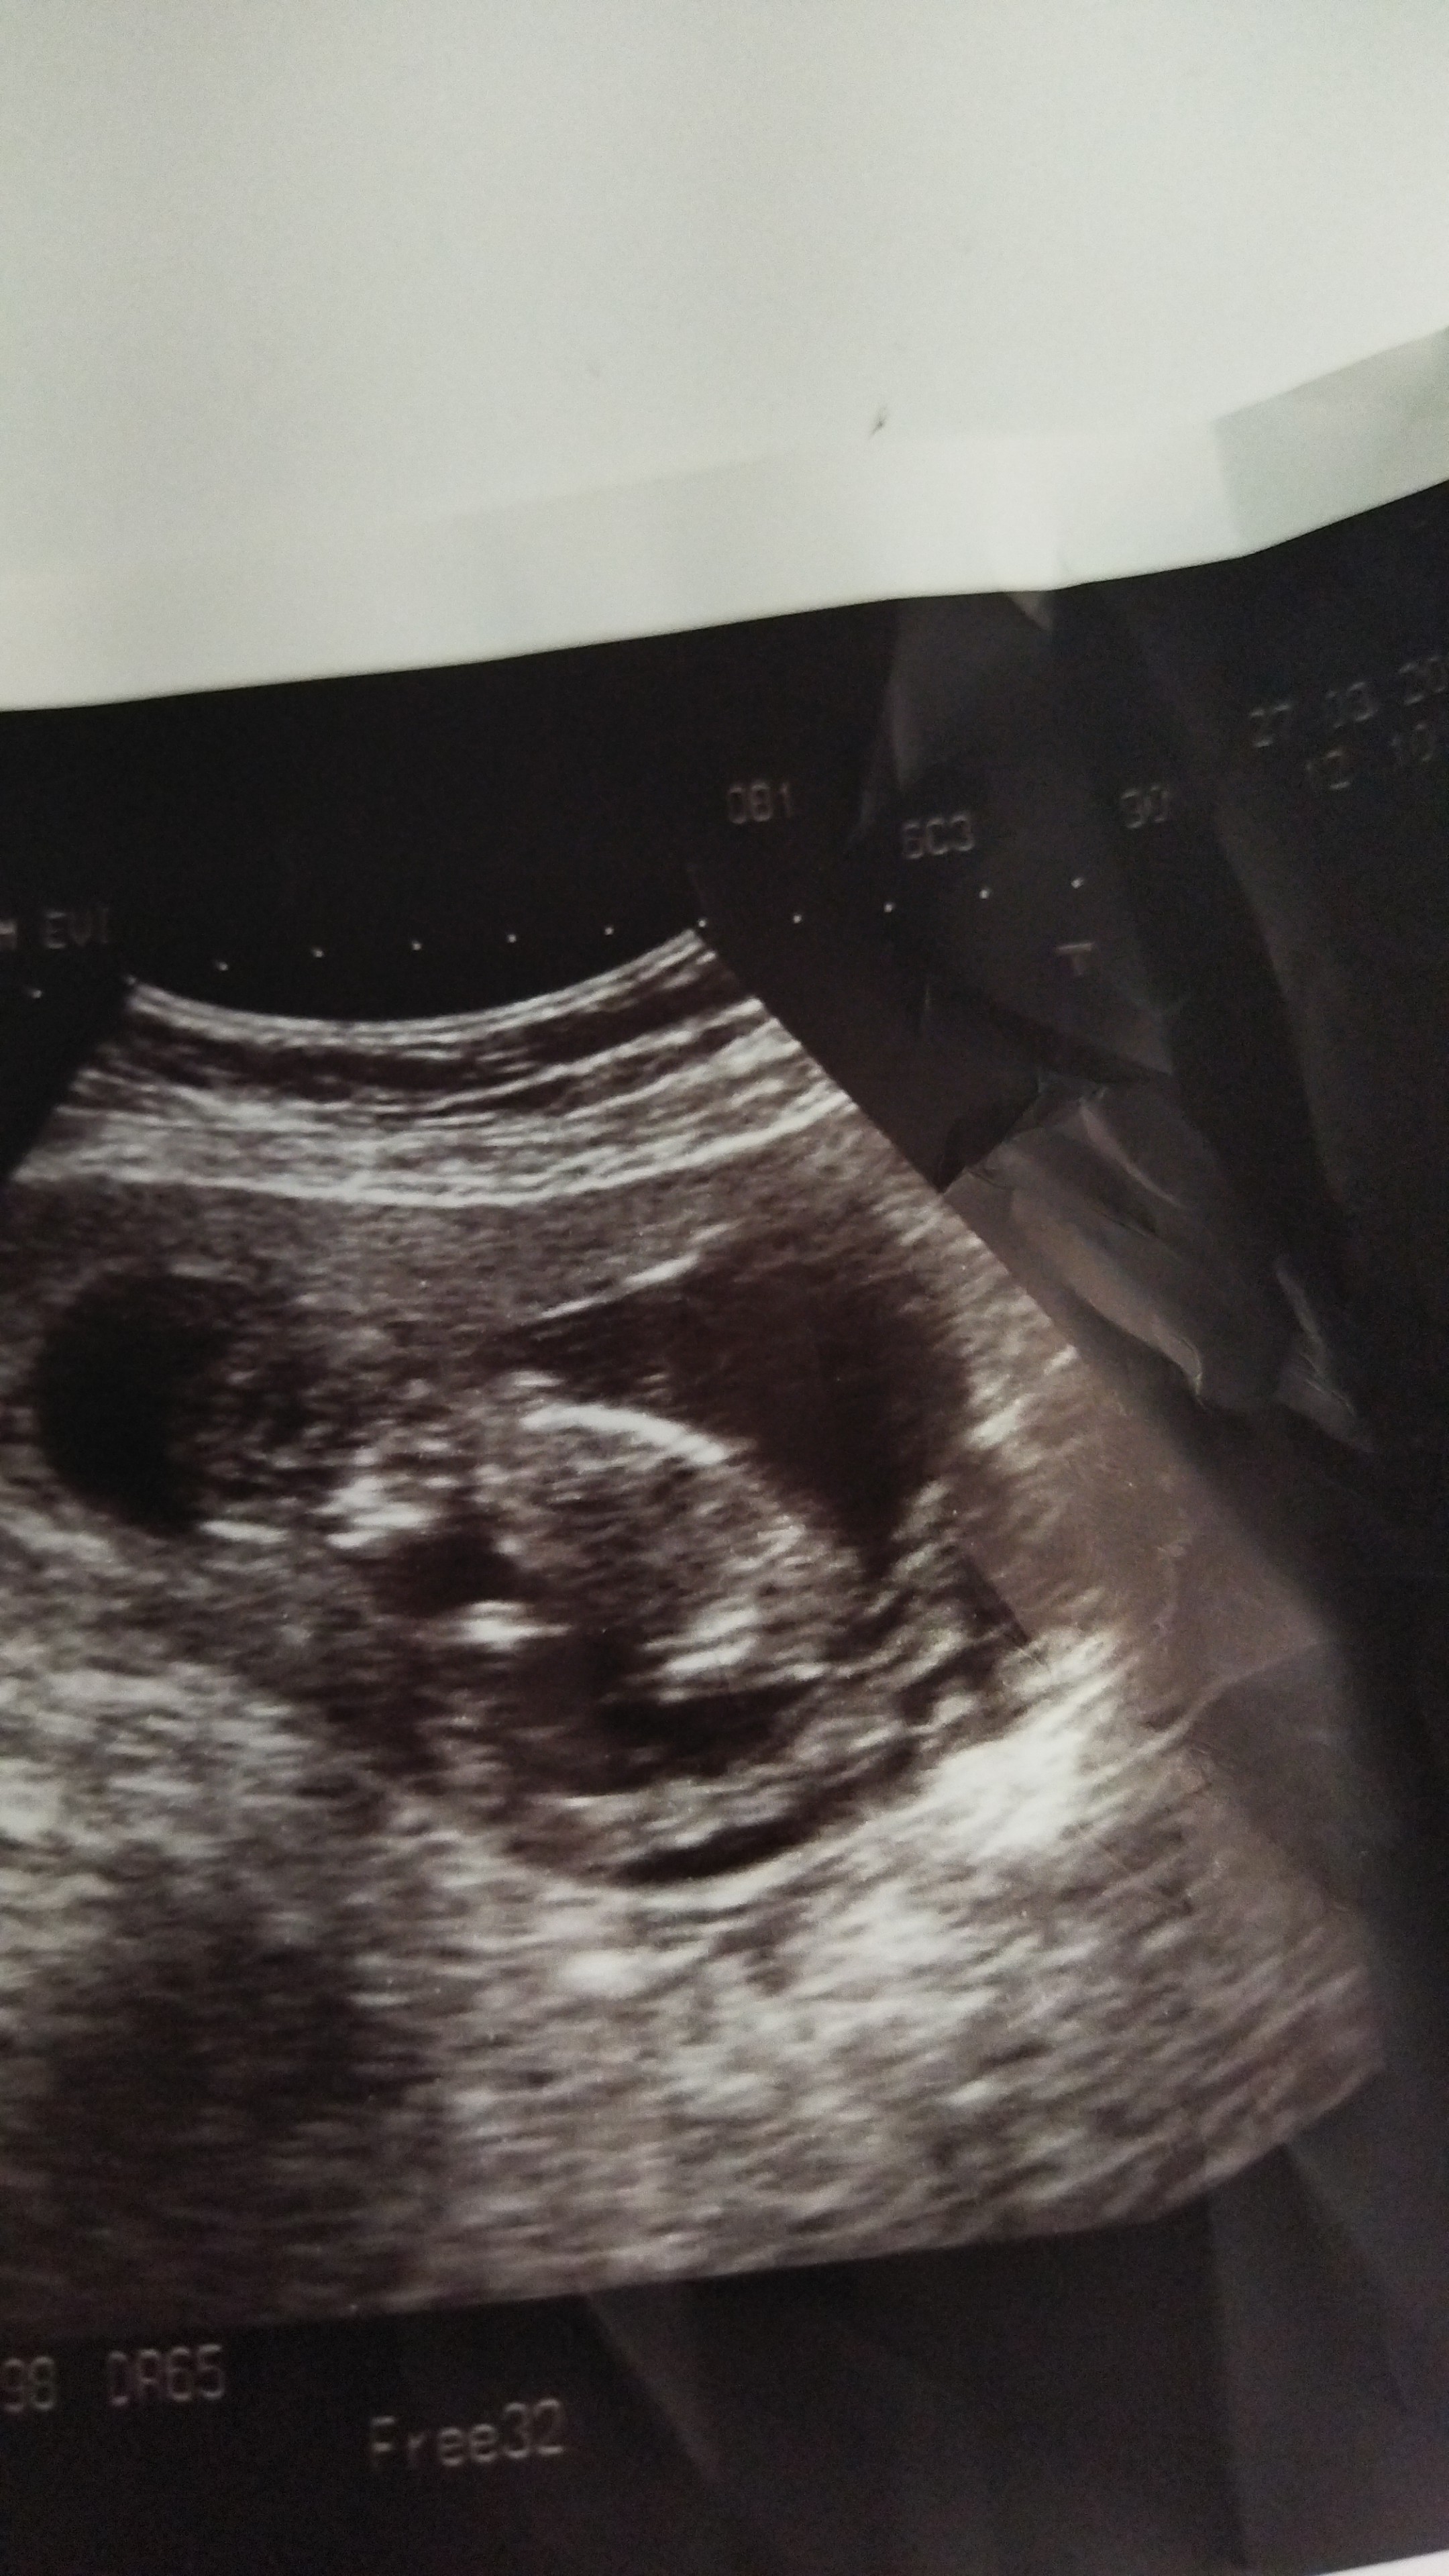

Cinsiyet tahmininde buluna bilirmisiniz .

Konu Başlığı Cinsiyet tahmininde buluna bilirmisiniz .

Amin bı kızım var bı tanede oğlum olsun istiyorum hayırlısı sağlikli olsunda eşim erkek hissediyor kizimdada kız demişti doğru hissetti bundada erkek hissediyorum diyor bakalım.

Dr söylemedim cnm sanki kıza benziyo ama

Hayır söylemedi tahmini vardı ama net olmadan söylemek istemedi